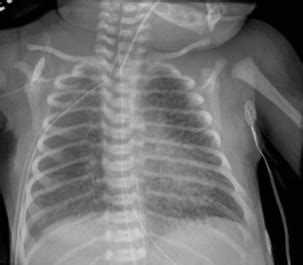

Okay, let’s get down to the nitty-gritty of how pulmonary interstitial emphysema radiology actually looks on a chest X-ray . This is often the first line of imaging used. When a radiologist looks at an X-ray of a patient with PIE, they’re scanning for specific patterns. One of the classic signs is the appearance of linear lucencies, which are essentially dark lines on the X-ray film. These lines represent air tracking within the interstitial tissues. Imagine tiny air bubbles or streaks running through the lung tissue, separate from the normal branching pattern of airways and blood vessels. Another key finding can be a ‘cystic’ or ‘bubble-like’ appearance, where larger pockets of air have accumulated in the interstitial space, sometimes looking like clusters of small balloons. You might also see signs of lung hyperinflation, where the lungs appear larger than normal, often because air is getting trapped. Sometimes, PIE can lead to a condition called pneumothorax, which is air in the space outside the lung, between the lung and the chest wall. This is a serious complication and appears as a dark space separating the lung from the chest wall on the X-ray. The diaphragm might also appear flattened due to the hyperinflation. It’s important to note that PIE can sometimes be subtle on an X-ray, especially in its early stages or if it’s mild. The radiologist has to be really vigilant and compare the current X-ray with previous ones if available to spot any changes. They’re looking for deviations from the normal, healthy lung pattern, and PIE creates a very distinct set of deviations. It’s a diagnostic puzzle, and the X-ray provides the primary pieces to solve it. The clarity and detail needed to spot these subtle linear lucencies and cystic changes are what make the radiologist’s expertise so vital in interpreting these seemingly simple images.